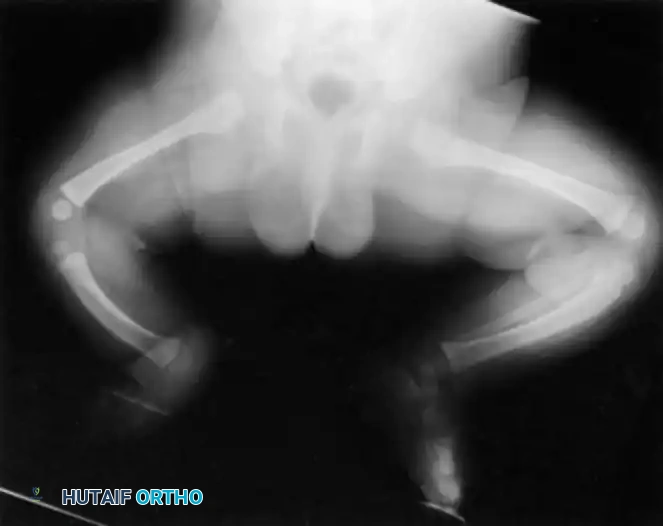

This condition represents a broad spectrum of deformities, ranging from the total absence of the tibia (the most severe form) to mild hypoplasia of the tibia (the least severe form). The incidence is exceedingly rare, estimated at one in 1 million live births, and the condition presents bilaterally in approximately 30% of affected patients.

Clinically, the involved leg is significantly shortened. The fibular head is often palpable, particularly if it is proximally displaced into the popliteal fossa. The foot is typically held in severe, rigid equinovarus, and the hindfoot is profoundly stiff.

In older children, the proximal tibial anlage may be palpable upon deep clinical examination, even if it is not radiographically visible. The knee is generally flexed, and in more severe deformities, profound quadriceps insufficiency causes an absolute lack of active knee extension.

- Type 1A Deformity: There is complete radiographic absence of the tibia and a hypoplastic distal femoral epiphysis compared with the contralateral normal side.

- Type 1B Deformity: There is no radiographic evidence of an ossified tibia; however, the distal femoral epiphysis appears more normal in size and shape. This distinction is critical because Type 1B deformities possess a proximal tibial cartilaginous anlage that can be expected to ossify over time. Modern imaging techniques, such as high-resolution ultrasound and MRI, are mandatory to identify this cartilaginous anlage.